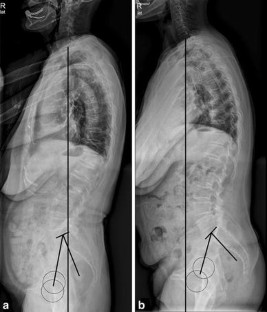

Fig. 1

Fig. 2

Fig. 3